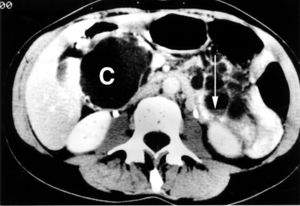

| كيسة پنكرياس كبيرة عند الناتئ الشصي للپنكرياس. | |

- الفحص بالتصوير المقطعي المحوسب قد يوفر اختبار التصوير معلومات مفصلة حول حجم تكيس الپنكرياس وبنيته.